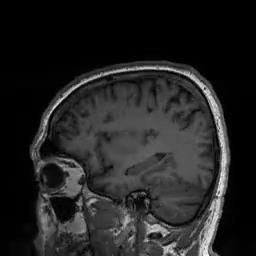

Conventional Deep Resolve

Deep Resolve is our AI-powered image reconstruction technology for MRI

• Enabling faster acquisitions, increased clinical productivity and better patient experience

• Increased image quality and resolution

• Reduced energy consumption per acquisition 2x